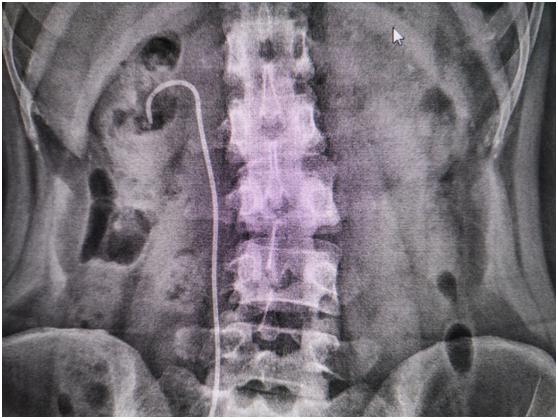

不久前,40多岁的江女士在体检时,意外发现右肾有一个分支生长的大结石,这个结石位于右肾中下盏,直径超过2.5cm。江女士回想起来,平时经常腰部酸胀不适,还反复发生尿路感染,之前一直以为是妇科炎症,或者是腰肌劳损,没想到竟是肾结石在作祟!

术中,输尿管硬镜和软镜双镜联合,并利用激光和气压弹道双能量粉碎结石后,再通过内镜配合负压吸引系统将肾脏内碎石经尿道吸出。整个手术不需要在腰部“打洞”。手术很成功,术后检查显示,肾结石已全部取出。